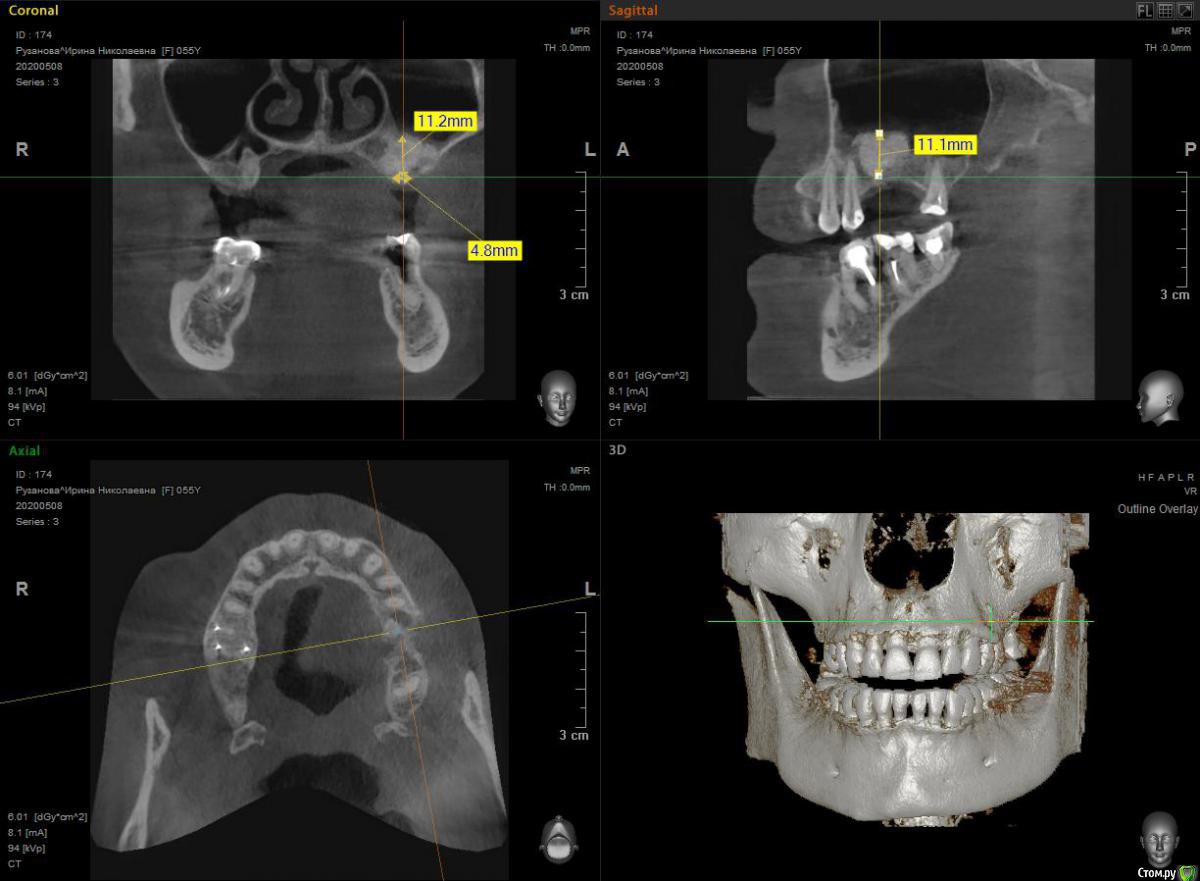

HAV Опубликовано 18 мая, 2020 Поделиться Опубликовано 18 мая, 2020 Всем здравствуйте. Была проведена операция ОСЛ, во время проведения операции была перфорация слизистой оболочки пазухи, перфорация закрыта интраоперационно мембраной Bio-Gide, внесен графт CeraBone. Первый снимок через 5 месяцев после операции - результат неудовлетворительный. Предпринята попытка повторно выполнить ОСЛ, старался максимально заполнить пустоты графтом, но как видно на снимке полностью исправить ситуацию не удалось. На даннный момент прошло 6 месяцев после последней операции. Интересует ваше мнение - возможно ли в данной ситации установка имплантата в позиции 26 зуба? Устанавливать имплантат в позиции 27 зуба пациенткка не хочет. Ссылка на комментарий

Bier Опубликовано 28 мая, 2020 Поделиться Опубликовано 28 мая, 2020 Интересует ваше мнение - возможно ли в данной ситации установка имплантата в позиции 26 зуба? возможно 2 Ссылка на комментарий